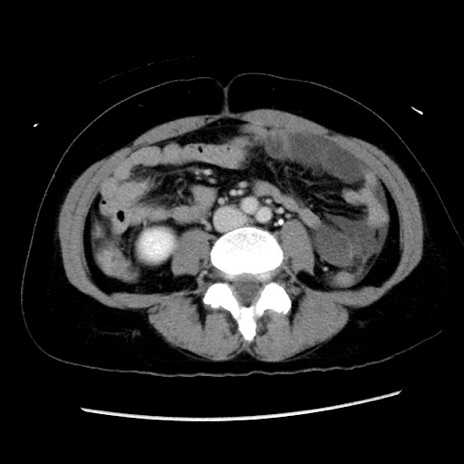

矢状断像